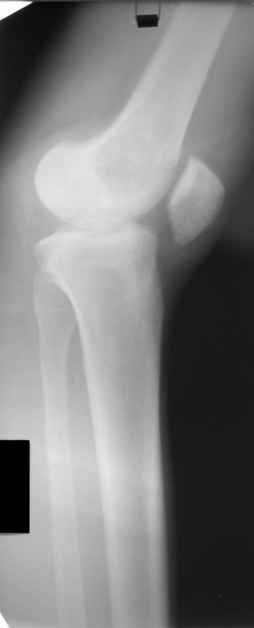

Больной Н., мужчина 18 лет с укорочением бедра и рекурвацией коленного сустава. Из анамнеза: огнестрельное сквозное пулевое ранение бедра 9 лет назад в н/3 левого бедра. Раны зажили без гнойных осложнений. Жалобы на укорочение левой нижней конечности и нестабильность в коленном суставе. При обследовании выявляется рекурвация коленного сустава. Абсолютное укорочение порядка 5см, стоя 8 см (за счет рекурвации). Имеется умеренный компенсаторный сколиоз. С передне-наружной стороны располагается рубец от входного отверстия, с задне-медиальной стороны от выходного. Можно предположить повреждение при травме зоны роста бедренной кости и задне-внутренних стабилизирующих структур коленного сустава. Предлагается обсудить тактику лечения: начать с удлинения бедра или со стабилизации коленного сустава, а также - на каком уровне производить удлинение бедра.A male 18 years old with shortened femur.Trauma 9 ears ago: gunshot wound with bullet of the left knee. It Is Reeked have healed without festering complications. The patient have shorter femur and recurvatum instability of knee joint. Absolute shortening is 5 cm, at standing up 8 cm (genu recurvatum). The input scar is situated on the antero-lateral side and output scar is on the postero-medial side. It is possible to expect damage by trauma of the growing zone of the femur and back-internal stabilizing structures of the knee joint. We discuss the treatment options: to begin with lengthening of the femur or preferably with stabilizations of the knee joint. What is the optimal level to produce the lengthening of the femur in this case.